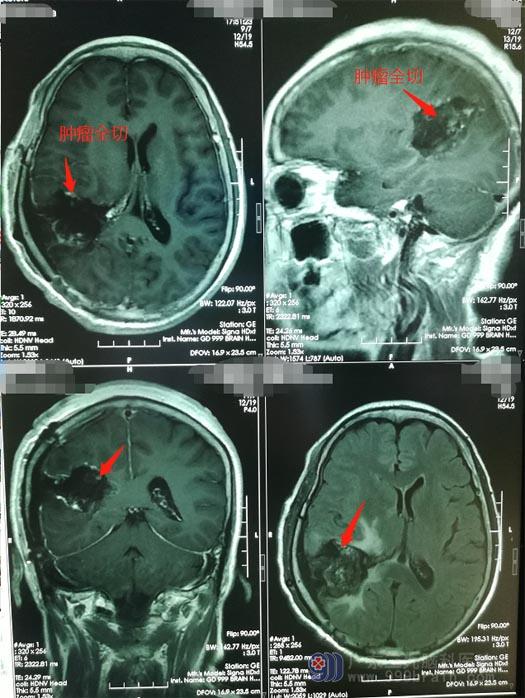

医院副院长、神经外五科主任鲁明认为患者的右侧颞顶叶占位考虑胶质瘤,肿瘤体积大,约50mm×39mm×47mm,手术指证明确,可以择期手术。术前准备妥当后,在全麻下行“右侧颞顶叶、侧脑室后角占位性病变切除术”,经过5个小时的奋战,顺利完成手术。术后MRI显示肿瘤已全部切除。

术后的李阿姨无言语、肢体功能障碍。病理结果:胶质母细胞瘤,WHO Ⅳ级,属于最高级别的恶性肿瘤,早期发现、及时手术切除干净,术后配合放射治疗、化学治疗可以极大地延长患者的生存期。